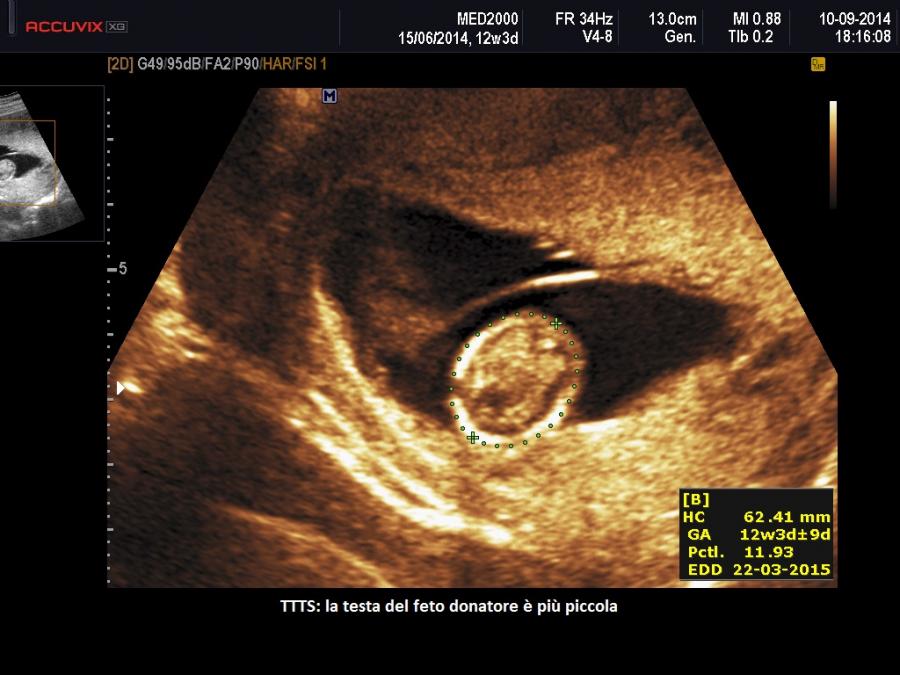

A 11-14 settimane si sospetta una TTTS quando: